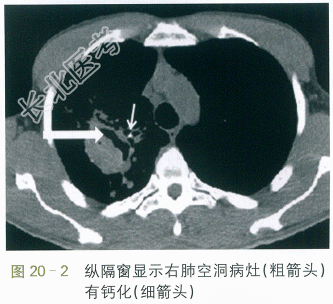

CT检查:右上肺见空洞,空洞内壁无液平,外周见斑片状影,纵隔窗显示空洞病灶有局限性钙化,左肺舌叶见小斑片状影伴支气管气象,右肺中叶也见少许渗出影伴小叶中心结节有树芽征。考虑两肺炎症,结核不能除外。如图20-1、图20-2、图20-3所示。